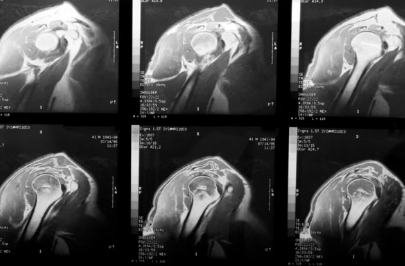

Imagerie

L'IRM ou l'arthroscanner permettra de faire le diagnostic et savoir si les tendons sont réparable